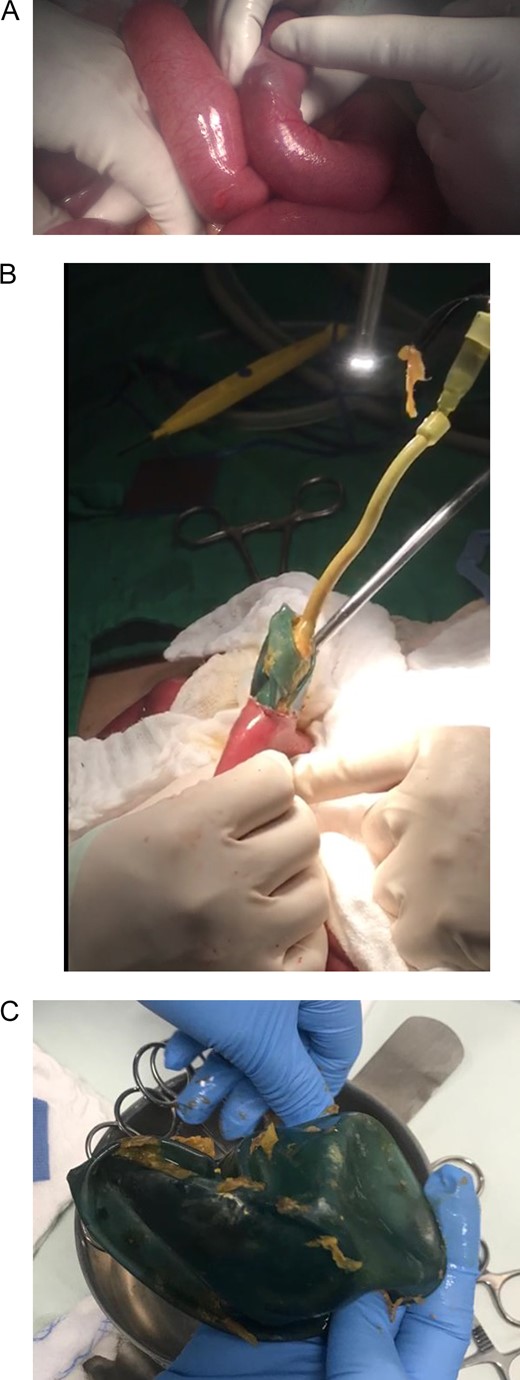

Bowel obstruction due to the migration of the deflated intragastric balloon was suspected. Following a laparoscopic approach, the intestinal loops were dilated, and 100 ml of inflammatory fluid were noticed in the abdominal cavity. However, the definite site of obstruction could not be accessed (Fig. 2). Due to this, a laparotomy was decided. There was an important dilatation of all the loops of the small bowel, and the bowel walls were thickened but no perforation was detected. Near the ileocecal valve, a clear bulging of the bowel wall caused by the deflated impacted balloon was externally visible. A 3 cm transverse enterotomy was performed and the deflated gastric balloon was gently pulled out. The enterotomy was subsequently closed and the rest of the procedure was completed without complications (Fig. 3).

(A) Laparoscopy, showing dilated intestinal loops. (B) Laparoscopy, showing dilated intestinal loops and free inflammatory fluid.